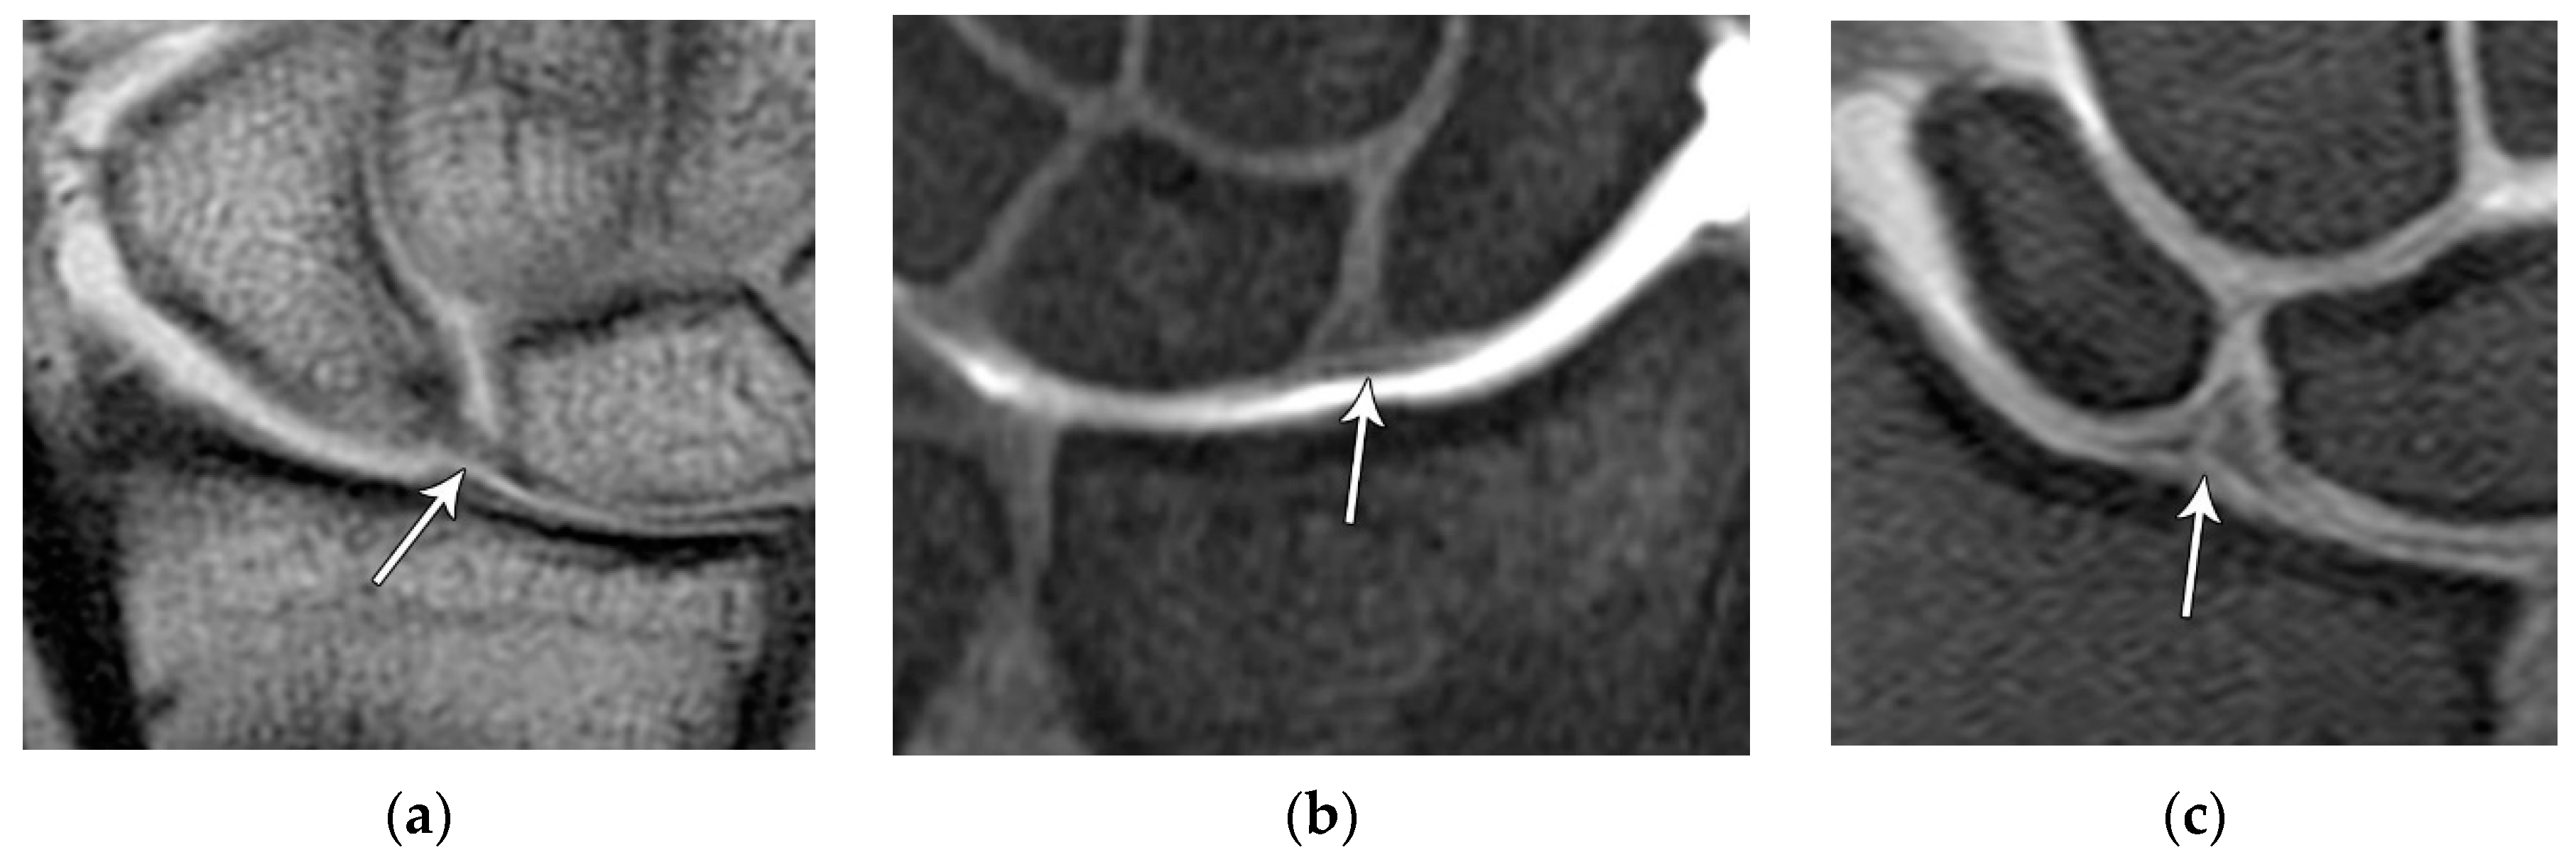

The scapholunate ligament can be thought of as having 3 separate components: proximal, dorsal, and volar (Figure 20) [2,14]. Tears are often traumatic in etiology (e.g., fall on outstretched hand or FOOSH) and associated with symptoms. The proximal component is also known as the “central membranous component” due to its location and composition (Figure 21A). Partial tears or degenerative perforations of this membranous portion are common and usually are asymptomatic. Typically, this portion has a triangular, meniscal projection distally (Figure 21B, C). The dorsal component is the thickest and has the most significant role functionally (Figure 22). The volar component is thin and weak, and therefore is not of great biomechanical importance and isolated injury is uncommon.

Figure 21. (a) Coronal T1 MR image showing a normal linear morphology of the proximal scapholunate ligament (SLL). (b) In a different patient, coronal PD FS MR image showing a normal triangular morphology of the proximal SLL. (c) In a different patient, coronal PD FS MR image showing an additional normal triangular morphology of the proximal SLL with a tear.